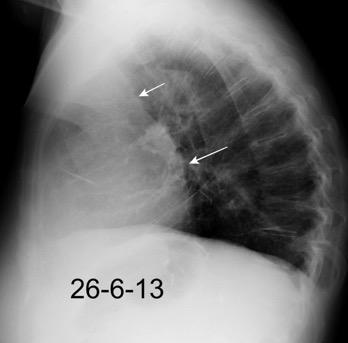

Carcinoma de mama con derrame pleural e implantes metastáticos

Makis W et al. Spectrum of Malignant Pleural and Pericardial Disease on FDG PET/CT. AJR. 2012